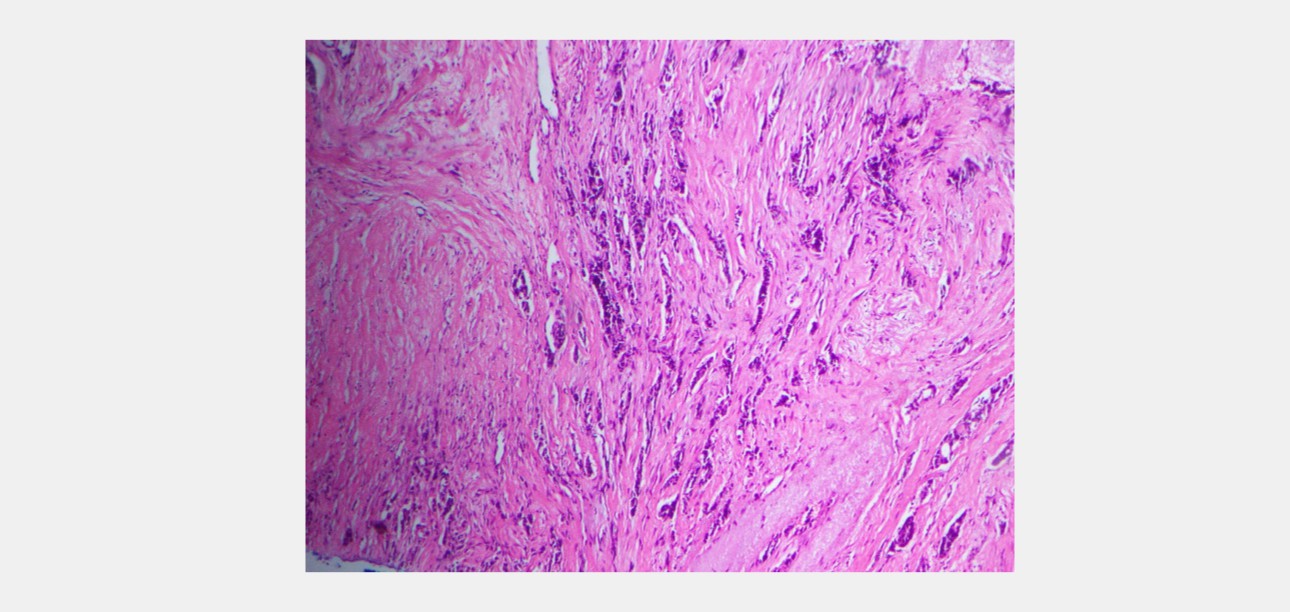

Histology Findings

6 core biopsy samples were taken. It showed an invasive carcinoma of the breast, composed of tubular structures, cords, and trabeculae of cells within a desmoplastic stroma. Tubule formation is minimal. The tumor cells have moderately pleomorphic vesicular nuclei. The mitotic count is 4/2 mm2. The cytoarchitectural features place the tumor in Nottingham grade II.

Malignant tissue is stiffer than benign breast tissue due to the high proliferative index resulting in high cellular density. This principle is utilized in elastography to identify suspicious lesions. The combination of B-mode and SWE increases the specificity in diagnosis from 61% to 79%, and the positive predictive value from 53% to 67% [1]. Few studies have proven that the tissue adjacent to the lesion showed more stiffness than the lesion itself. They have reported that the peripheral tissue of malignant lesions is typically stiffer than that of benign lesions because the former has abnormal stiff collagen fiber, which is related to cancer fibroblasts, as well as infiltration of cancer cells into the surrounding tissue [2]. Mindray Resona 7 system has introduced an option to measure the shell around the specific ROI. In the Resona 7 system, the cut-off value in differentiating benign and malignant was reported as 98.66 kPa in the measurements where a shell of 2 mm in thickness was included [3]. The two cases show that the elastography values were compatible with the histology findings. The measurements taken in the lesionŌĆÖs center were incompatible with patient A's histology findings. It may be due to the center of cancer undergoing necrosis and cystic degeneration. Studies have proven tumor active proliferation can lead to local ischemia, necrosis, and cystic changes affecting the average hardness of tissues [4].